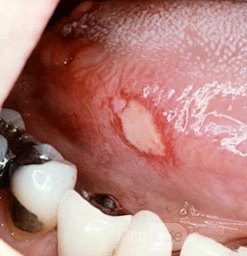

Loét Apthous

Viêm miệng áp tơ đặc trưng bởi các "vụ" loét nông đau tái phát ở niêm mạc miệng. Nguyên nhân gây ra tình trạng này vẫn chưa được biết. Các tổn thương cấp tính này được phân định rõ ràng với phần gốc phủ fibrin màu vàng được bao quanh bởi một quầng đỏ. Vết loét màu trắng cực kỳ khó chịu ở rìa bên của lưỡi này nằm trong vết loét áp tơ. Đặc điểm ban đỏ xung quanh vết loét được thể hiện rõ ràng. Các tổn thương này tự lành mà không để lại bằng chứng nhìn thấy được.